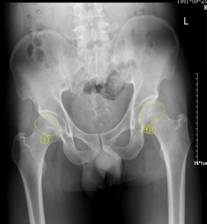

新技術:瀘州市中醫(yī)院成功開展富血小板血漿(PRP)術——早期股骨頭壞死患者福音股骨頭壞死是一種原因不明的常見骨科疾病,根據(jù)不同的發(fā)病程度和部位分區(qū)有不同的治療方法。近日,瀘州市中醫(yī)院成功開展的富血小板血漿微創(chuàng)手術(簡稱:PRP)為早期股骨頭壞死患者帶來福音,同時也為保髖治療增添了新的治療方法。診斷:...